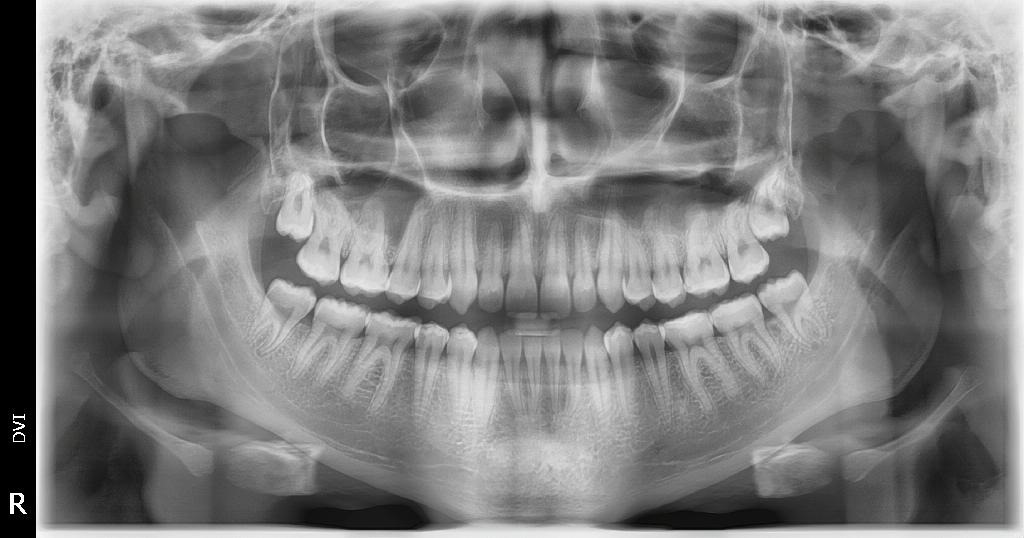

Since this forum has only high-IQ accomplished Indian doctors, should I remove my wisdom teeth based on this X-RAY?

Jewish dentists want them removed but I think its bullshit just like circumcision

Dont listen to those jews. Only remove if causing pain